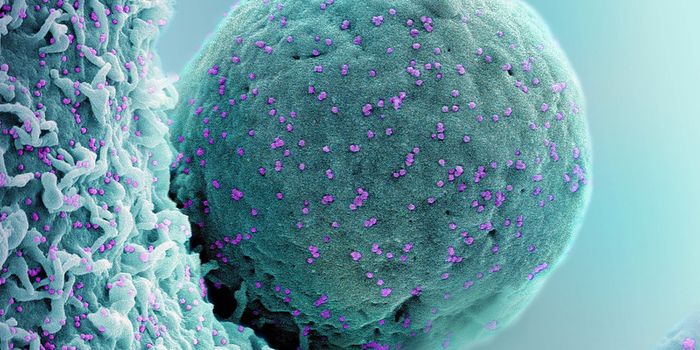

SEP 08, 2024MicrobiologySARS-CoV-2, the pandemic virus that causes COVID-19, has mutated endlessly since it burst on the scene in late 2019. An ...

AUG 27, 2024MicrobiologySince the start of the COVID-19 pandemic, the virus that causes the illness - SARS-CoV-2 - has had a practically infinit ...